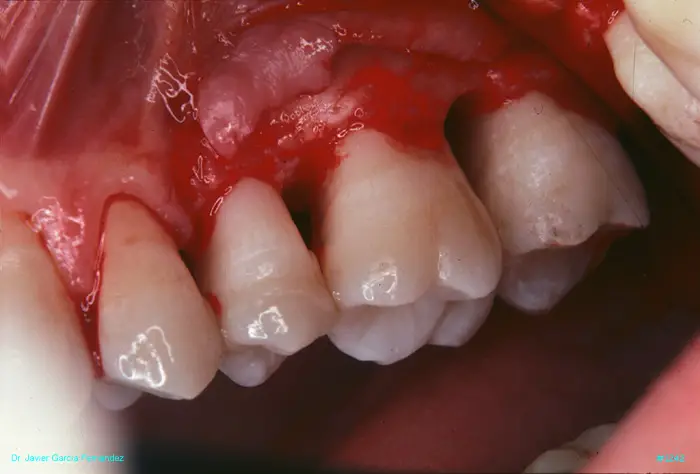

Atlas of Surgical Techniques in Periodontics. Chapter III. Atlas de Técnicas Quirúrgicas en Periodoncia